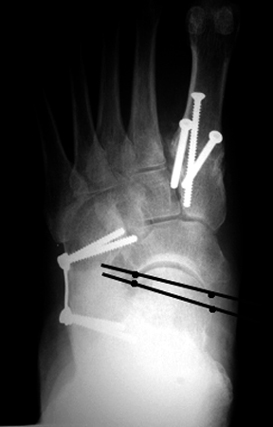

A 66 Year Old Female With Pes Planovalgus Our Hindfoot X Ray Image Download Scientific Diagram